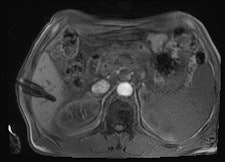

All procedures were performed using a wide-bore 1.5-tesla MR system (Magnetom Espree, Siemens Healthcare). A radiofrequency-shielded liquid-crystal display monitor was installed next to the magnet for real-time monitoring. During the procedures, imaging was performed with the use of a flexible four-channel body-array surface coil and a loop coil, and biopsies were performed with MR-compatible puncture needles. To obtain the specimen, an MR-compatible biopsy device (MRI Biopsy Handy, Somatex Medical Technologies) was used in 36 cases. After placing the MRI-compatible puncture needle in the magnet, two intramuscular biopsies were performed using a non-MR-compatible spring-loaded biopsy gun (ASAP, Boston Scientific) outside the magnet. During the biopsy, vital parameters were monitored using an MR-compatible patient monitor (Invivo 4500 MRI, Invivo Research).

In nine cases -- eight soft-tissue, one liver -- MR fluoroscopy was used to define the entry site, and the physician used a fingertip or water-filled syringe as a marker. In 29 cases -- 11 soft-tissue, 18 liver -- a marker capsule (Adalat, Bayer) was affixed to the supposed entry side with adhesive tape, and the position was corrected after application of conventional sequences. After sterile draping, administration of local anesthesia and skin incision, an MR-compatible puncture needle (14-18 G) was placed subcutaneously outside the magnet.